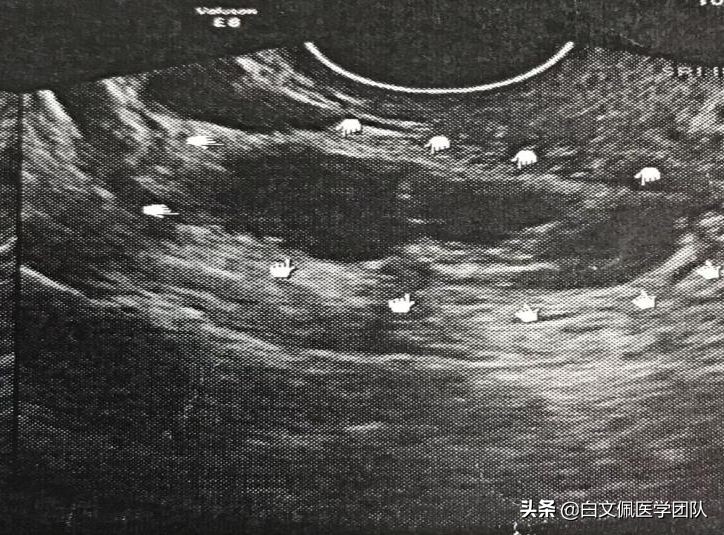

双侧卵巢子宫内膜异位囊肿,在子宫后方形成“对吻”,引起渐进性加重的痛经和不孕。

术前三维超声清楚地显示了囊肿和子宫的关系,使我们能够更加精心地准备和设计手术。